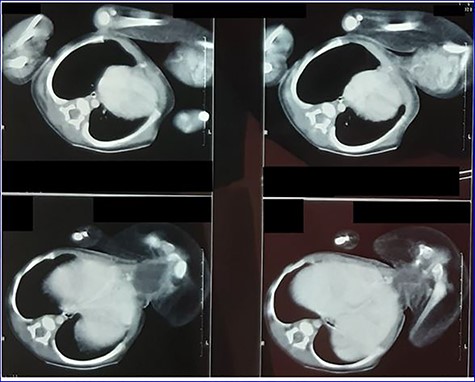

Contrast enhanced computed tomography (CT): (Figs 3 and 4)

No obvious anomalies in the autosite viscera. No clear vascular or visceral contact between the twins. The parasite consists of pelvic and two femur bones with cystic formation may represent a bladder. A single pelvic kidney is suspected with some intestinal loops in the pelvis.

Contrast-enhanced CT scan image showing parasite’s viscera and bony parts.